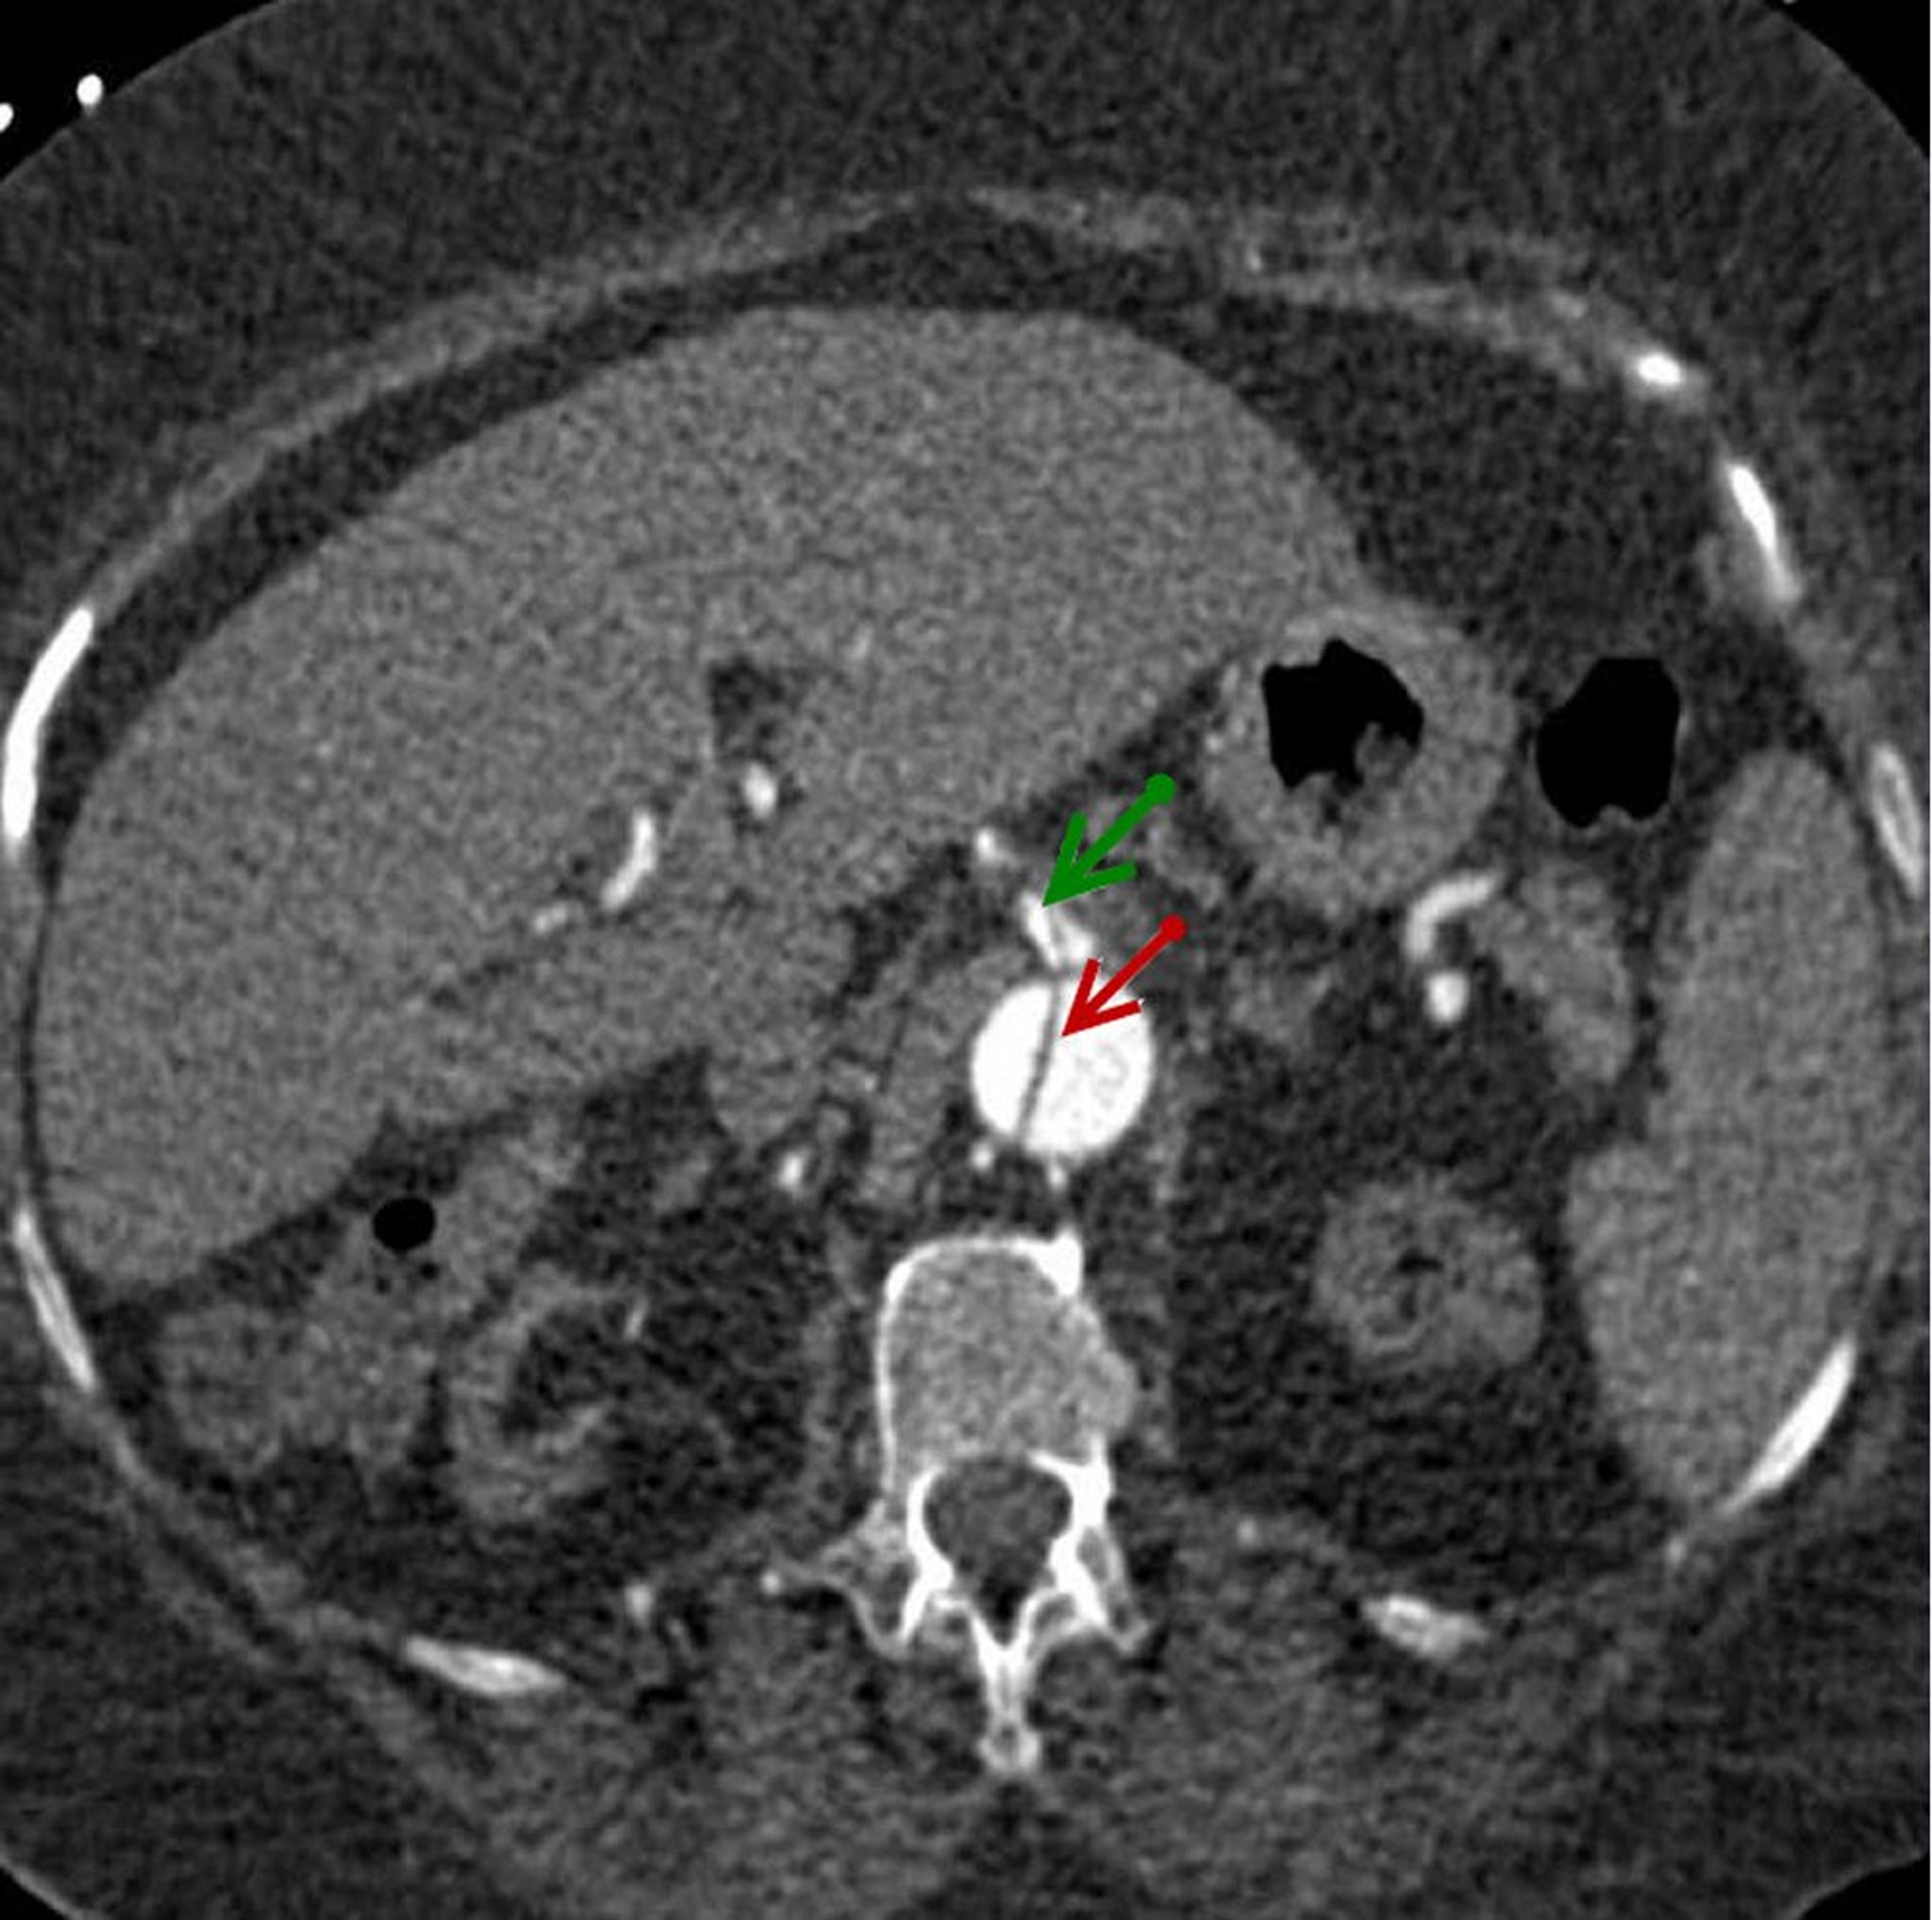

Imagen axial del colgajo de disección en la aorta abdominal descendente (flecha roja) que se extiende hacia la arteria mesentérica superior (flecha verde).